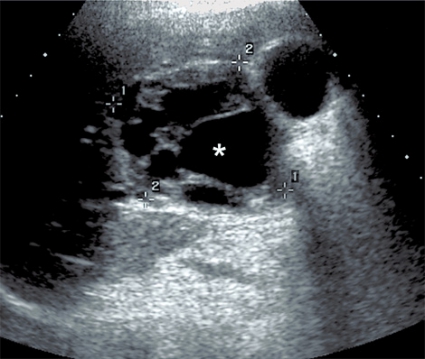

Fall 1. En 11-årig svenskfödd flicka insjuknade våren 2004 med intermittent hosta och blodtillblandat expektorat. Under sommaren utfördes en datortomografi (DT) av lungorna i Turkiet. Antibiotika gavs och föräldrarna informerades om att hon hade ekinokockos. DT på Karolinska universitetssjukhuset i Huddinge visade en oval cystisk struktur, 3,5 cm i diameter, i vänster lungas lingula. En liknande struktur påvisades i vänster underlob. I levern fanns en 5 cm stor cysta (Figur 1). Serologi var positiv avseende ekinokockos. Flickan vistades vartannat år en längre tid hos sin farfar i en by i centrala Turkiet. Detta är ett område med högendemisk förekomst av Echinococcus granulosus. Farfar är fårfarmare som slaktar hemma och ger sina hundar slaktavfall. I november 2004 fick flickan albendazol (Zentel) motsvarande 14 mg/kg/dag uppdelat på två doser. Ny DT efter fyra månader visade att cystorna i lungan minskat kraftigt i storlek. Efter ett års behandling hade de nästan helt försvunnit. Albendazol gavs i 18 månader. Ultraljud fyra år senare visade att cystan i levern minskat till 2,7 cm, och den bedömdes som inaktiv (CE4).

Hos människa orsakar E granulososus-infektion långsamt växande, icke invasiva cystor. Den vanligaste lokalisationen är levern (60–80 procent), följt av lunga (15–20 procent), mjälte (5 procent), skelett/muskulatur (4 procent) och övriga organ (2–5 procent) [1-3]. De som har cystor i lungan har ofta även cystor i levern. Vanligast är dock en enda solitär cysta i levern. Cystorna växer 1–10 (50) mm/år, och det finns en stor tendens till spontanläkning som ökar med tiden. Levercystor verkar växa långsammare än lungcystor [1]. Aktiva cystor innehåller vanligen dottercystor (Figur 4) och ett stort antal några tiondelar av en millimeter stora protoscolices. När cystan degenererar försvinner dottercystorna, innehållet blir homogent och väggen förkalkas. Ekinokockcystor i lungan kan inte förkalkas. Cystornas aktivitet kan klassificeras enligt ett modifierat WHO-schema baserat på ultraljudsundersökning [2, 3]. De orsakar en inflammatorisk reaktion i den omgivande vävnaden, vilket leder till bildning av en fibrotisk kapsel av varierande tjocklek utanför själva cystmembranet och ibland till uppkomst av fistlar till omgivande strukturer, framför allt gallgångar.

Radiologisk utredning av ekinokockcystor har flera målsättningar. Den ska bidra till diagnostiken och till en anatomisk kartläggning av utbredning och eventuella komplikationer, bedöma cystans viabilitet och underlätta preoperativ planering. Den radiologiska diagnostiken av ekinokockcystor i levern har centrerats runt ultraljud men har på senare tid ofta ersatts med DT och MR. Radiologiska fynd som talar för ekinokockcysta utgörs framför allt av cystvägg med dubbelkontur, multivesikulärt utseende och väggförkalkningar (talar för inaktiv cysta). Viktigt att komma ihåg är att kalcifiering av väggen förekommer inte bara vid inaktiva (CE4 och CE5) cystor utan även i upp till 50 procent vid alla stadier [7]. WHO-klassifikationen av ekinokockcystor grundas på ultraljudsundersökning men kan överföras till antingen DT eller MR [2, 3]. Cystans relation till gallvägar, kärl och extrahepatisk vävnad bedöms enklast med DT eller MR. Om fistulering till gallvägar misstänks kan MR med kolangiopankreatikografisekvenser och i vissa fall endoskopisk retrograd kolangiopankreatikografi (ERCP) bidra till noggrann anatomisk kartläggning inför planerad resektion [8].